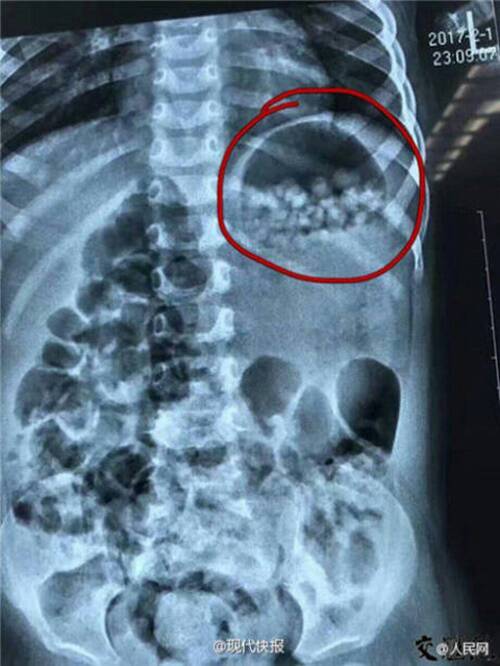

ซึ่งกว่าที่เธอจะทราบว่ามันคือเบบี้คริสตัล หนูน้อยก็ทานเข้าไปแล้วกว่า 280 เม็ด จึงต้องเร่งนำตัวส่งโรงพยาบาลด่วน โดยผลจากการเอกซเรย์เผยให้เห็นว่าในช่องท้องของหนูน้อยเต็มไปด้วยเบบี้คริสตันมากมาย แต่เคราะห์ดีที่มันยังไม่ทันได้ดูดน้ำและขยายตัวในท้อง หนูน้อยจึงปลอดภัย ทั้งนี้ทางแพทย์ได้ให้ยาช่วยขับออกจากร่างกาย และจะขับออกจนหมดภายใน 24 ชั่วโมง